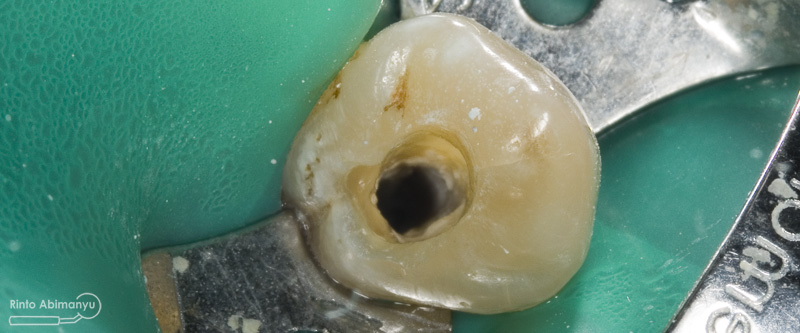

Pada pemeriksaan intra oral terlihat gigi 23 dan 24 mengalami karies dan cukup banyak sisa makanan terjebak disana…

Pertama saya lakukan anestesi infiltrasi dan kemudian memasang rubber dam untuk isolasi daerah kerja, dilanjutkan pembersihan karies dan pembukaan kamar pulpa.. Pada kasus ini pengerjaan dilakukan langsung pada dua gigi…